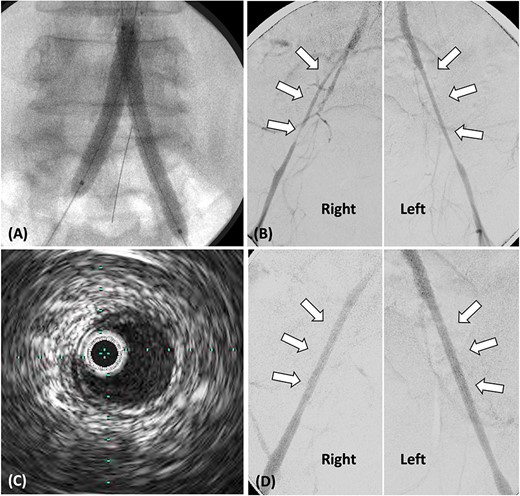

Subsequently, stent grafts were placed from the abdominal aorta to the bilateral CIA. First, balloon dilatation was performed using 4.0 mm × 100 mm SHIDEN HP (Kaneka Medical Products, Osaka, Japan) from the abdominal aorta to bilateral CIA. The sheath inserted in the bilateral CFA was switched to a 7-Fr long sheath (25 cm), whereas the guidewire was changed to a 0.035-inch Radifocus guidewire. Second, Gore Viabahn VBX stent-grafts (W. L. Gore and Associates Inc., Flagstaff, AZ, USA) were inserted from the abdominal aorta at the IMA level to both CIAs (right: 8 × 59 mm and 8 × 59 mm; left: 8 × 59 mm and 7 mm × 59 mm). Finally, both VBX stent-grafts were individually dilated with a 10 mm × 40 mm Mustang balloon (Boston Scientific, Marlborough, MA, USA) and then molded using a kissing balloon technique with an 8-mm balloon [2] (Fig. 2A). To prevent IMA occlusion, IMA was shielded with a 4.0 mm × 40 mm Sterling balloon (Boston Scientific, Marlborough, MA, USA) during the procedure. Express SD stents (4 × 19 mm and 4 × 19 mm; Boston Scientific, Marlborough, MA, USA) were eventually placed at the origin of the IMA.

(A) Stent grafts placed from the abdominal aorta to bilateral CIA using the kissing stent technique. (B). Stenosis observed in both EIA, treated with plain balloon angioplasty only. (C) Post-balloon dilatation intravascular ultrasound reveals the absence of calcification or atheroma in both EIA. (D) Angiography post-balloon dilation reveals no EIA stenosis and calcification or atheroma.

Following stent-graft placement, angiography revealed severe EIA stenosis and delayed blood flow (Fig. 2B). Both EIA lengths were carefully dilated using a 5.0 × 100 mm SHIDEN HP balloon. After balloon dilatation, delayed blood flow resolved. Intravascular ultrasound (IVUS) finding post-balloon dilatation confirmed the absence of calcification or atheroma in both EIA, suggesting that EIA was pseudo-stenosis and no additional stents were inserted (Fig. 2C and D).